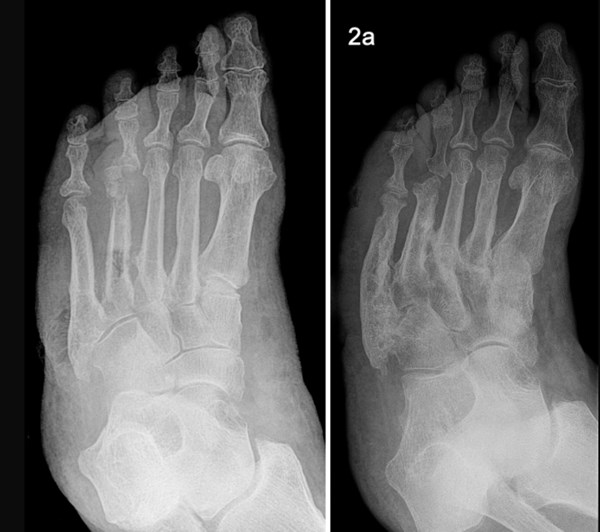

• Plain X-ray:  Useful to determine location - the most commonly affected joints in Charcot arthropathy are in the midfoot region (ie, the cuneiform/metatarsal area) [12] (Figure 22 and 23).

Figure 22: Charcot foot. X-rays of the same foot, showing progression of disease over 2 years. Fractures in the cuneiform/metatarsal area [120].

Figure 23: Osteomyelitis of the first metatarsophalangeal joint [111]